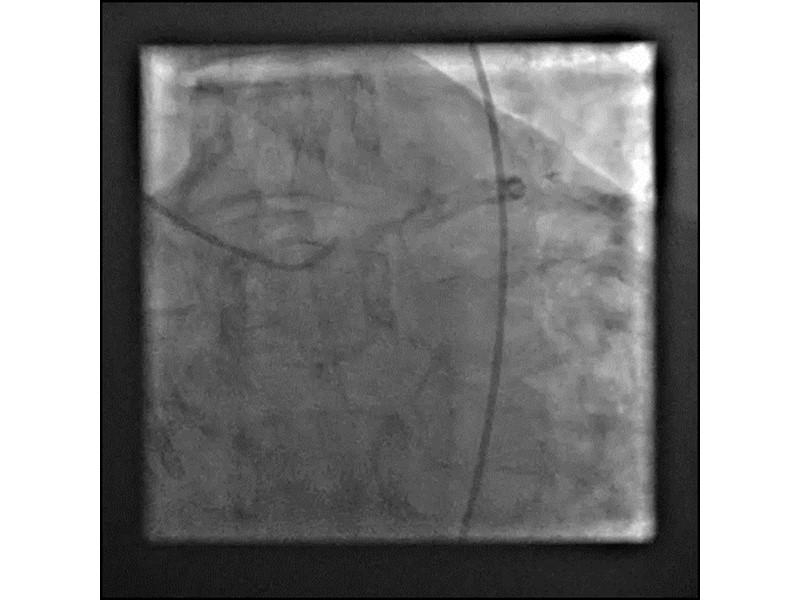

Distal left main stenosis: how to treat optimally with dedicated bifurcation stent BiOSS Lim C. Case-based session

- To get acquainted with the new technology for bifurcation lesion

- To learn about multiple technological options with dedicated bifurcation stent for complex left main bifurcation lesions